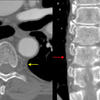

coronal CT